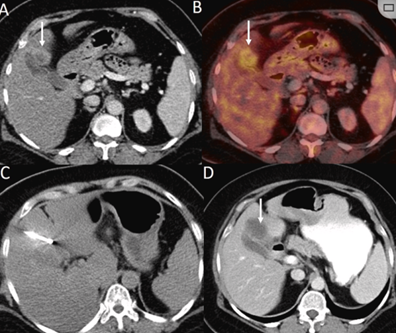

CT引導(dǎo)的冷凍消融

(b) 冷凍消融術(shù)中影像顯示冰球完全覆蓋病變。(c) 19個月后隨訪,沒有發(fā)生局部腫瘤進展。完全消融率為97%(66/68);2名患者均接受了額外的冷凍消融,隨后實現(xiàn)完全消融。平均隨訪期為 12.8 個月(范圍:3-27 個月)。所有患者均接受影像復(fù)查(CT 或 MRI)。11個病灶(16.2%)檢測到局部腫瘤進展,6、12和18個月時的累積局部腫瘤進展率分別為4%、8.2%和20.5%。8例出現(xiàn)遠處肝內(nèi)或肝外病變的患者接受經(jīng)動脈化療栓塞、經(jīng)動脈化療栓塞加射頻消融治療或全身化療。

主要和次要并發(fā)癥發(fā)生率分別為3.5%(2/57)和22.8%(13/57)。并發(fā)癥主要表現(xiàn)為局部皮膚凍傷、中度氣胸、發(fā)熱,僅有少數(shù)患者接受治療,多數(shù)患者自行恢復(fù)。所有患者能耐受圍手術(shù)期疼痛,VAS 評分范圍在 1-3 分之間(平均 1.65分)。3例患者術(shù)后疼痛加重,VAS評分達到4~5分,患者口服止痛藥后逐漸緩解。所有患者術(shù)后1天血常規(guī)、白細胞計數(shù)均升高,血小板均有不同程度下降,但變化值均在正常范圍內(nèi)。肝功能1個月后逐漸恢復(fù)到正常水平。